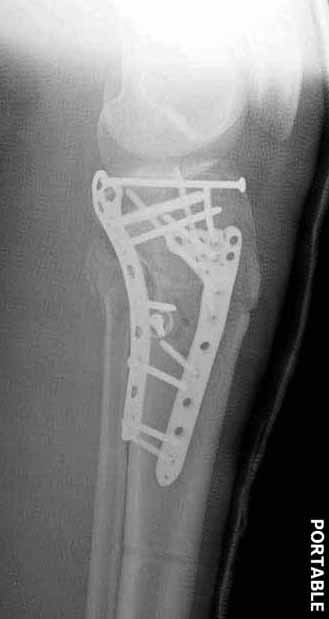

Для изолированных переломов медиального тибиал плато, фиксацию можно провести “медиальной пластиной”. Некоторые компании, например Smith & Nephew делают медиальные и медиально-задние пластины, но они мягкие, и легко можно создать нужный контур. Жесткость создается за счет фиксации жесткими пластинами, например экстра артикулярной пластиной для дистального плеча от Synthes. Медиальный доступ тоже не из легких, надо работать между pes and medial gastroc.

Если у вас, кроме пластины, нет другого альтернативного варианта, тогда, учитывая мягкотканые проблемы с наружной стороны, я бы рекомендовал операцию делать в два этапа. Преимущества, сперва репозиция и фиксация перелома с медиальной стороны, а затем, после улучшения состояния мягких тканей, зафиксировать с латеральной стороны. Современные пластины имеют латеральный Jig для перкутанных мини доступов.

В приложении этапы фиксации Both Column Fx и пластиной Synthes для плеча при переломе медиального мыщелка.